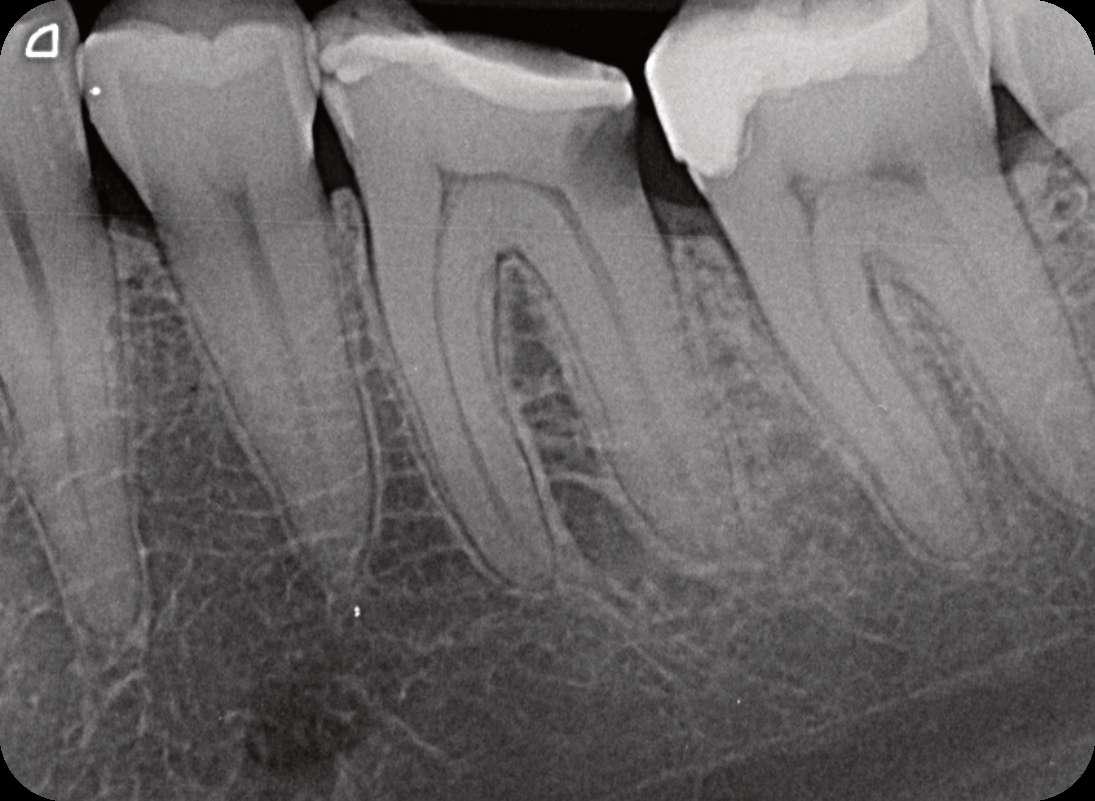

Präoperativ

Der erste untere, linke Backenzahn zeigt einen Zerfall auf dem distalen Teil mit dem Symptom einer irreversiblen Pulpitis. Zuerst wird der Karies entfernt und der Zahn wird mit einer temporären Füllung wieder aufgebaut. Danach wird der Kofferdam platziert und der Zugangshohlraum steht.

Vier Kanäle wurden mit dem SX EdgeTaper Platinum eröffnet. Auch der koronale Teil wurde mit dem S1 EdgeTaper Platinum erweitert. Arbeitslänge und Durchgängigkeit werden mit einer #10 K-Feile erreicht. Die A #15 K-Feile wurde verwendet, um Länge und Durchgängigkeit zu gewährleisten. Dank der Technologie von EdgeNedo war ich im Stande, die Feile für eine komfortable Formgebung vorzuformen, auch wenn die Öffnung reduziert wurde. S1, S2, F1 und F2 EdgeEndo Platin wurde bis zur gesamten Länge des Kanals eingebracht.

Während der Isthmus-Reinigung zeigte sich zwischen den mesialen Kanälen ein zusätzlicher Kanal. Die Formgebungsphase erfolgte schnell und effizient dank SX zum F2.

Das Röntgenbild zeigte eine große Länge und einen gemeinsamen Ausgang für zwei der drei mesialen Kanäle.

Die Wurzelfüllung erfolgte mit einer einzigen Kegeltechnik unter Verwendung des BUSA EndoSequence Bioceramic Sealer. Das Post-OP-Röntgen zeigt sehr hohe Dichte in der gesamten Länge der Wurzelfüllung.